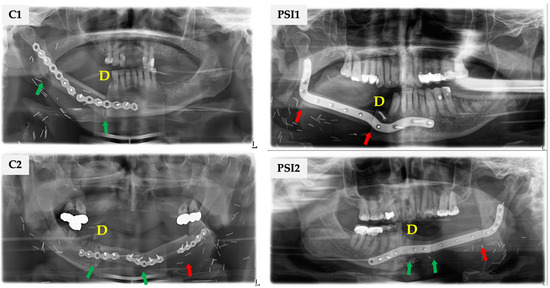

| OU: M ↔ F and F ↔ F, n (%) | 44 | 45 | |

| COU | 38 (86.4) | 29 (64.6) | |

| IOU | 6 (13.6) | 16 (35.6) | 0.017 |

| OU: M ↔ F and F ↔ F, n = all junctions (%) | 120 | 129 | |

| COU | 114 (95.0) | 104 (80.6) | |

| IOU | 6 (5.0) | 25 (19.4) | <0.001 |

| OU: M ↔ F, n = only proximal and distal junctions, (%) | 88 | 79 | |

| COU | 82 (93.2) | 62 (78.5) | |

| IOU | 6 (6.8) | 17 (21.5) | 0.006 |

| OU: F ↔ F, n = only intersegmental junctions, (%) | 32 | 50 | |

| COU | 32 (100.0) | 42 (84.0) | |

| IOU | 0 | 8 (16.0) | 0.015 |